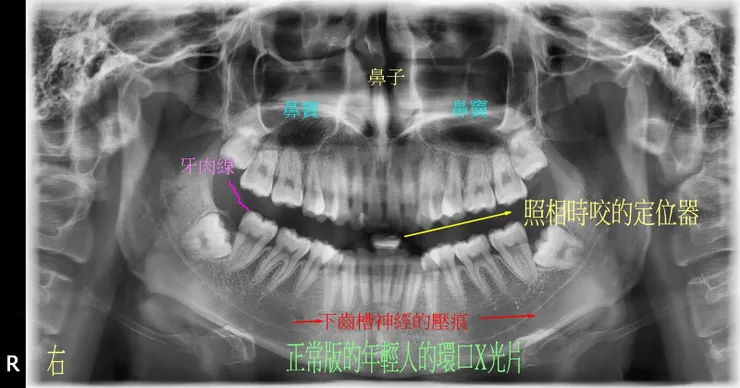

先來個正常版的(23歲,正常男性),當基準,解釋一些正常的解剖構造